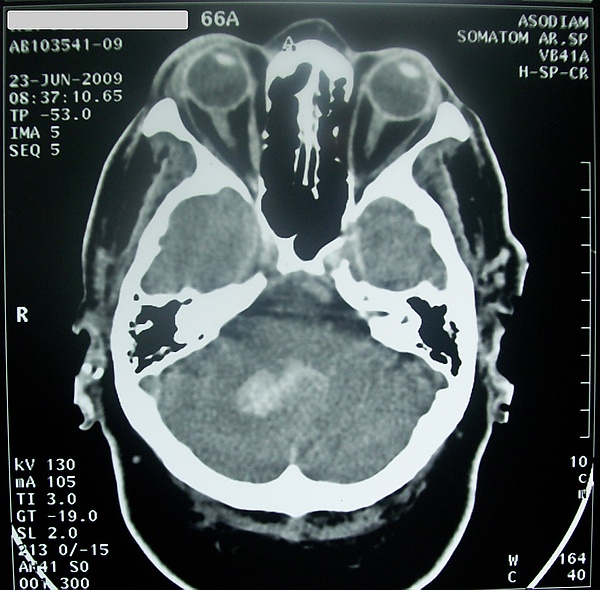

Кровоизлияние в мозжечок обычно проявляется головокружением, тошнотой и повторной рвотой при сохранении сознания. Больных часто беспокоит головная боль в затылочной области, у них обычно выявляются нистагм и атаксия в конечностях. При возникновении мозжечково-тенториального смещения или вклинении миндалин мозжечка в большое затылочное отверстие развивается нарушение сознания вплоть до комы, геми- или тетрапарез, поражения лицевого и отводящего нервов[43].

Вследствие ограниченности субтенториального пространства даже при сравнительно небольшом объёме повреждений мозжечка нередко развёртываются дислокационные синдромы с ущемлением продолговатого мозга миндалинами мозжечка на уровне затылочно-шейной дуральной воронки либо ущемлением среднего мозга на уровне намёта за счёт смещаемых снизу вверх верхних отделов мозжечка[44].